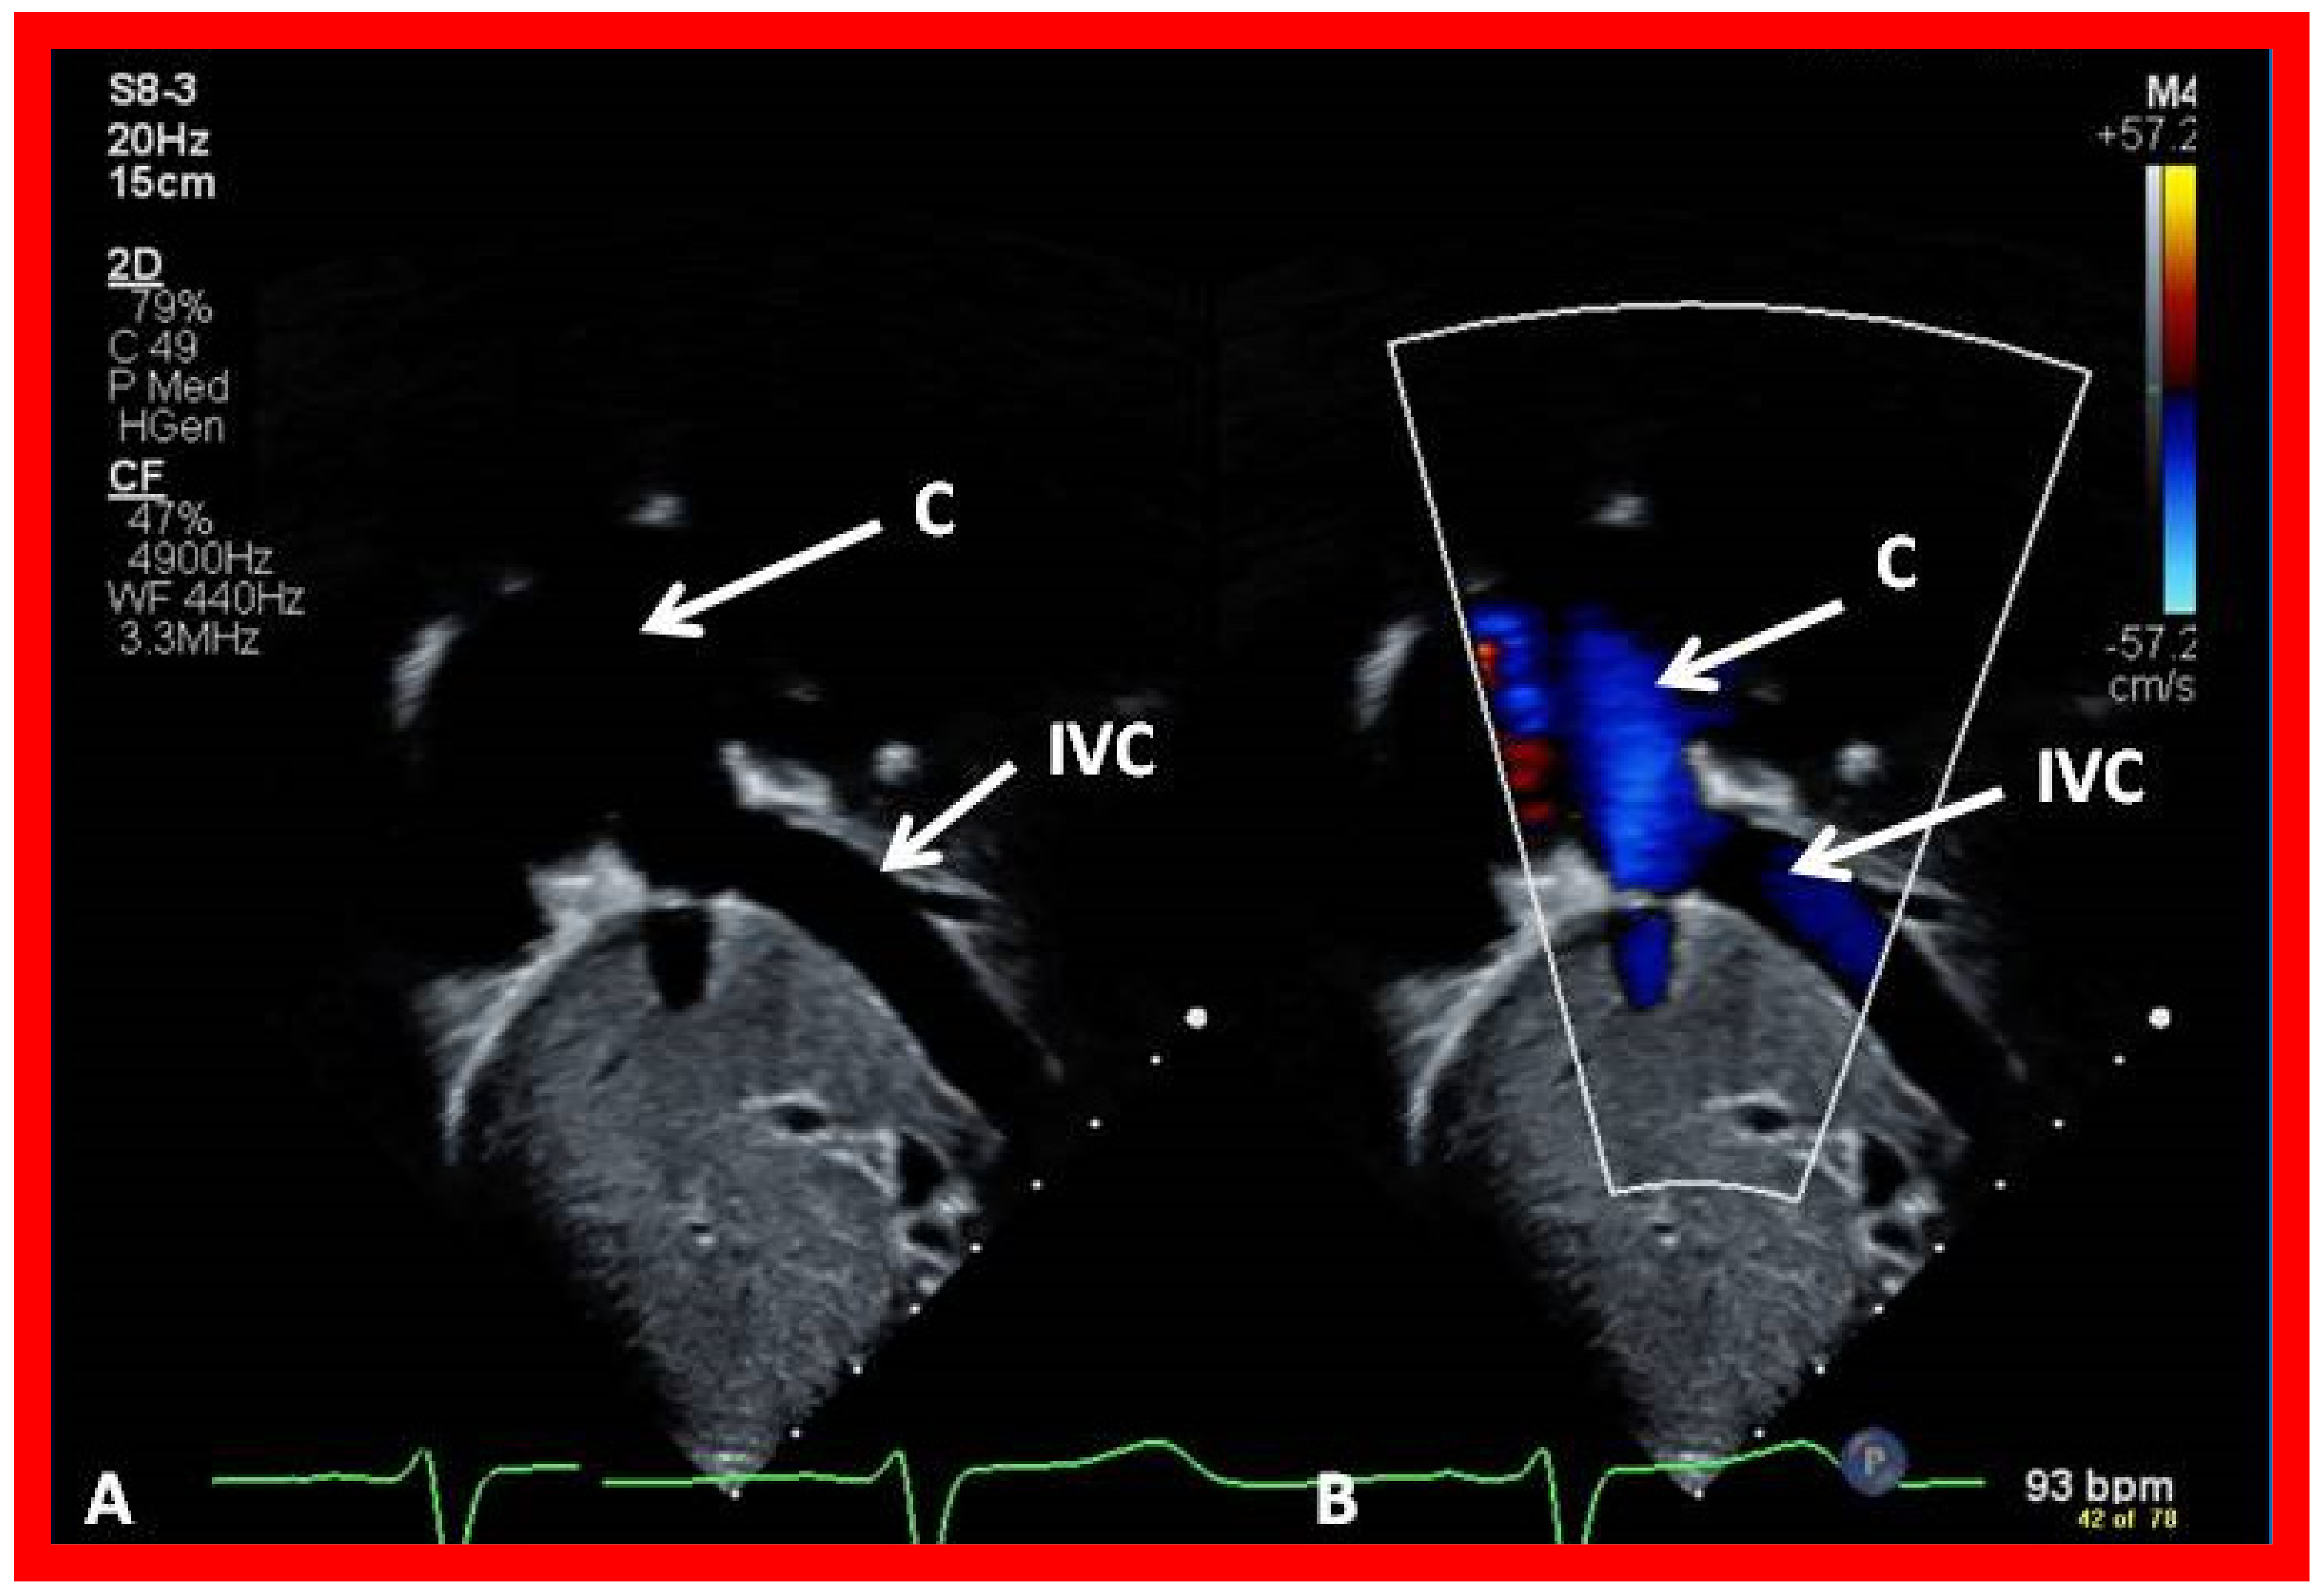

7. Echocardiogram

10.4.1. Stage IIIA

10.4.2. Stage IIIB